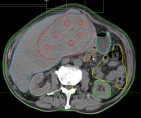

病例展示二:前列腺癌

XXX,男,64岁,主诉:间断性会阴部疼痛10月,确诊为前列腺癌7月。盆腔核磁:前列腺偏左侧异常强化占位,多考虑前列腺Ca,并左侧精囊腺受侵可能,盆腔左侧略大淋巴结。前列腺癌标志物提示:TPSA 88.67 ng/ml,FPSA 3.84 ng/ml。病检:(前列腺穿刺组织左侧)前列腺腺泡腺癌,Gleason评分4+3=7分;(前列腺穿刺组织右侧)Gleason评分3+3=6分。诊断:1、前列腺恶性肿瘤 双侧 腺泡腺癌Gleason评分4+3 =7分 cT3bN0M0 III期 KPS评分:80分。治疗方案:醋酸戈舍瑞林缓释植入剂 10.8mg 皮下注射、比卡鲁胺胶囊 50mg 口服 1次/天”全身治疗,并行前列腺癌碳离子治疗,剂量:57.6 Gy(RBE)/16 Fx。